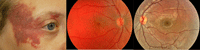

El síndrome de Sturge-Weber se caracteriza por la presencia de al menos dos de las siguientes anomalías: hemangioma facial (nevus flammeus), hemangioma intracraneal homolateral, hemangioma coroideo difuso homolateral, anomalías vasculares conjuntivales y epiesclerales homolaterales, y glaucoma.El hemangioma difuso de coroides aparece aproximadamente en un 50% de los pacientes con síndrome de Sturge Weber y en un 40% de los que presentan nevus flammeus o hemangioma facial. En general la tumoración coroidea es unilateral y homolateral al hemangioma facial. Se presenta como una lesión de color rojo anaranjado, de gran tamaño, localizada en el polo posterior con extensión hacia la región preecuatorial, que da lugar a una coloración del fondo de ojo denominada en “tomate ketchup”. Su espesor suele ser mayor en el área macular con los bordes mal definidos, a menudo muy difíciles de diferenciar de la coroides sana. En la ecografía en modo B aparece una masa difusa con solidez acústica en la coroides posterior, con su característico patrón de alta reflectividad en modo A. Otros signos a menudo asociados son la degeneración quística de la retina suprayacente, la dilatación y la tortuosidad de los vasos retinianos, y alteraciones en el EPR. Además, el hemangioma difuso de coroides puede complicarse con un desprendimiento exudativo de la retina, glaucoma neovascular y catarata secundaria. Si el hemangioma no cursa con desprendimiento de retina, puede pasar desapercibido en la exploración oftalmoscópica. El estudio comparativo de la coloración del fondo de ojo afecto con el ojo contralateral sano es un buen método para sospechar el diagnóstico4,5 (Figura 5).

Figura 5. Nevus flammeus y hemangioma difuso de coroides homolateral. Obsérvese la coloración intensa del fondo del ojo afecto.